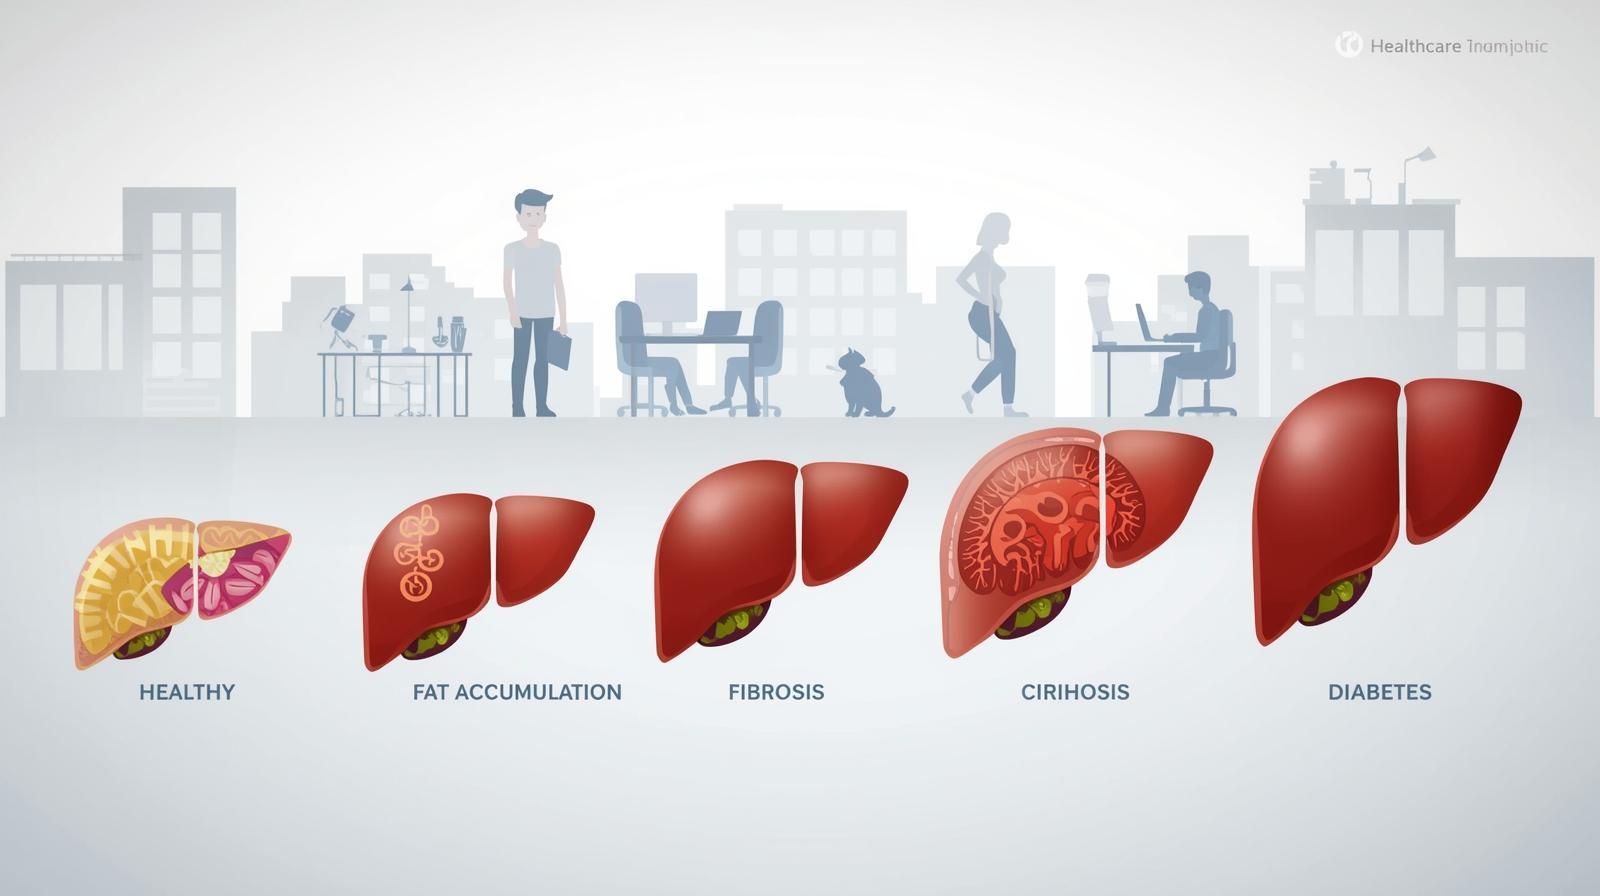

Non-Alcoholic Fatty Liver Disease is increasingly common worldwide and linked to obesity, diabetes, and metabolic syndrome. Recent research underscores that MASLD treatment centers on lifestyle modification and drug therapies targeted at metabolic risk factors.